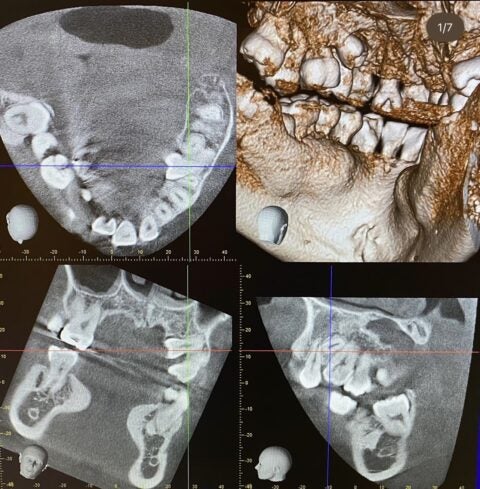

さて、本日は矯正前処置の埋伏歯の抜歯のご症例の紹介です!抜歯手術のが画像(モノトーン処理)がありますので、苦手な方はご注意ください。

過剰に口蓋側に偏移していてやや難易度の高い抜歯となります。